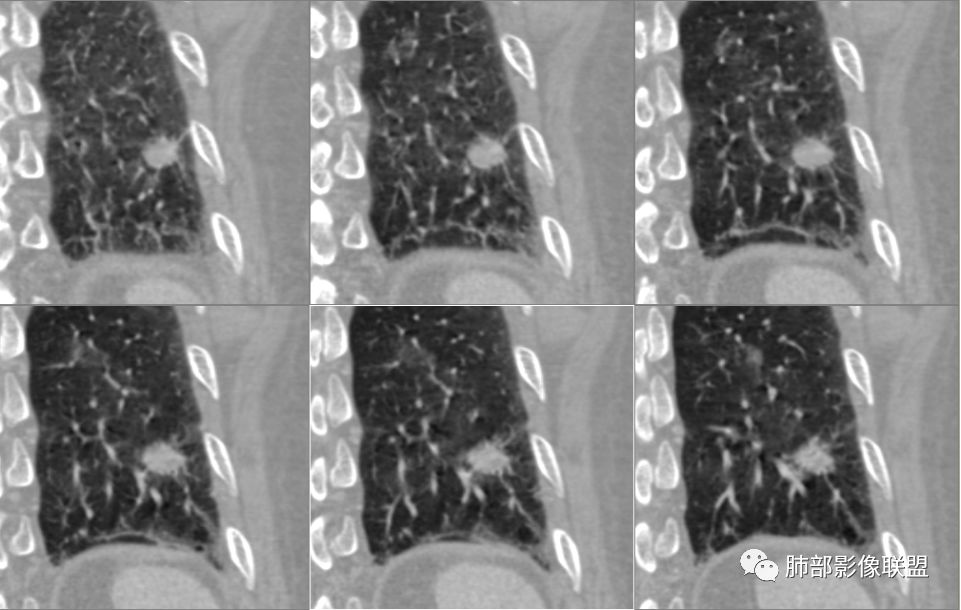

南边:

支气管截断。

支气管在门口堵塞恶性居多,结核有时也有。

空泡

分叶

血管纠集

毛刺

总体分析,支持恶性。

病例2肉瘤样癌的病理意见有些出乎预料,也充分说明病变及影像表现的复杂性。病灶小结节支气管截断、空泡、分叶、短毛刺、血管集束征等似乎均符合肺癌的影像特性。肺鳞癌及肉瘤样癌往往范围较小就可以出现坏死,但如果结节太小则很少能够在影像上观察到坏死区或空洞,没有增强扫描图像更是如此。